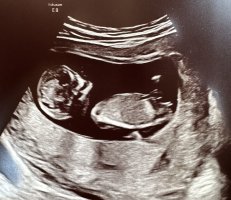

ja det vil jeg tro er en guttSniker fra mars. Her er min lille målt til 13+1. Er det en gutt?

ja det vil jeg tro er en gutt![]()